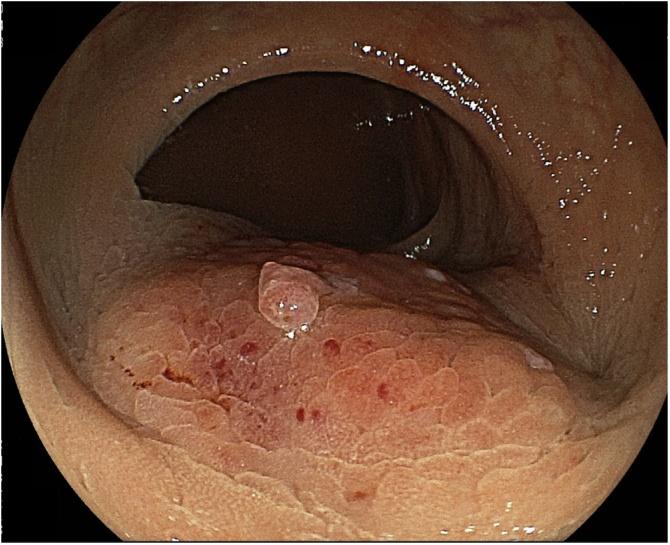

A 59-year-old woman complained of tenesmus and discomfort in the buttocks. Computed tomography revealed a 50-mm well-defined cystic mass in the presacrum and a 70-mm solid mass extending from the cyst into the rectum, vagina, and left sciatic spine. On T1-weighted magnetic resonance images, the cyst was unilocular and the mass was marginated with low intensity. On T2-weighted images, the mass had high intensity. A malignant presacral developmental cyst was diagnosed, without obvious metastasis. Using abdominal and parasacral approaches, Hartmann's operation was performed with multiorgan resection, including the sacrum, coccyx, left sciatic spine, internal obturator muscle, rectum, and uterine appendage. Histopathology of the excised specimen revealed a squamous cell carcinoma originating from the presacral epidermoid cyst.

Reports of malignant transformation of epidermoid cysts in the presacral space, as in the present case, are extremely rare. Because of their unusual location and slow growth, epidermoid cysts tend to remain asymptomatic. Because the patient had a malignant tumor with suspected invasion of adjacent organs, combination surgery was selected.